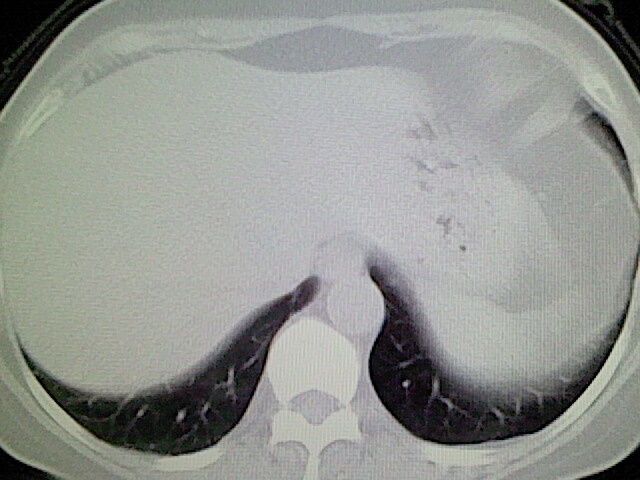

女,52岁,咳嗽,咳痰多日

左下肺陈旧纤维索条!

左肺舌段炎性改变

我见过几例,为炎症后纤维条索

慢性炎症后改变

考虑慢性炎性病灶粘连牵拉改变。

左肺舌叶纤维锁条病变。

左肺上叶下舌段炎症并局部胸膜反应。

左肺舌叶纤维索条影。

左肺舌叶段陈旧性病变

左肺舌段炎性反应。片子的质量太不好了。

左肺舌段炎性

炎性改变

左肺舌叶纤维索条影